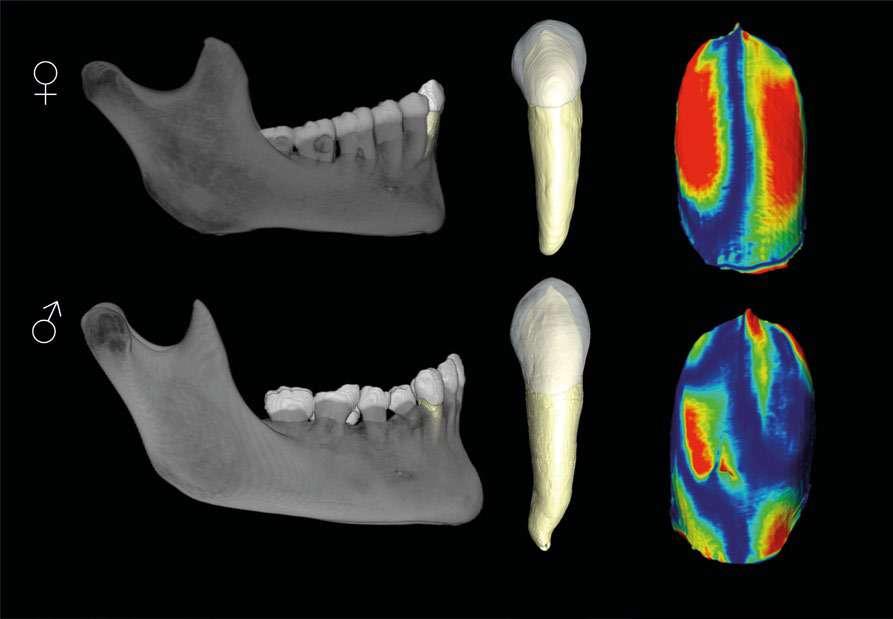

Los caninos revelan nuevas claves para la estimación del sexo en poblaciones humanas

Grupo de Antropología Dental del CENIEH